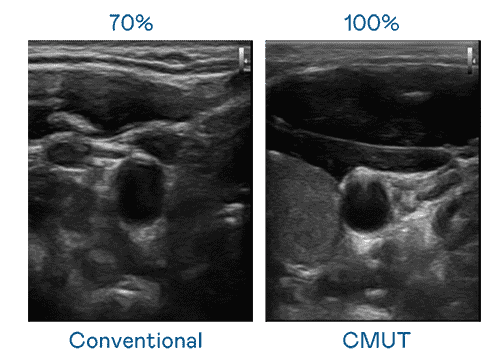

CMUT 技术是一种用电容式微机电元件来产生超音波讯号的技术。。。。与传统 PZT 压电式技术相比,,CMUT 频宽增加 30%,,,,更宽频的超音波讯号让影像解析度大幅提升,,是实现高影像品质医疗超音波扫描、、、、促进精准医疗发展的关键技术。。。。

大频宽带来超清晰影像

超音波影像的解析度高低,,首先取决于探头能发出的讯号频宽。。。至成国际 CMUT 可提供高清晰的超音波讯号,,,提供高频宽、、、高灵敏度、、影像纹理细节更高的超音波影像,,协助医护人员缩短影像判读时间及利用精准的医疗影像进行诊断。。。